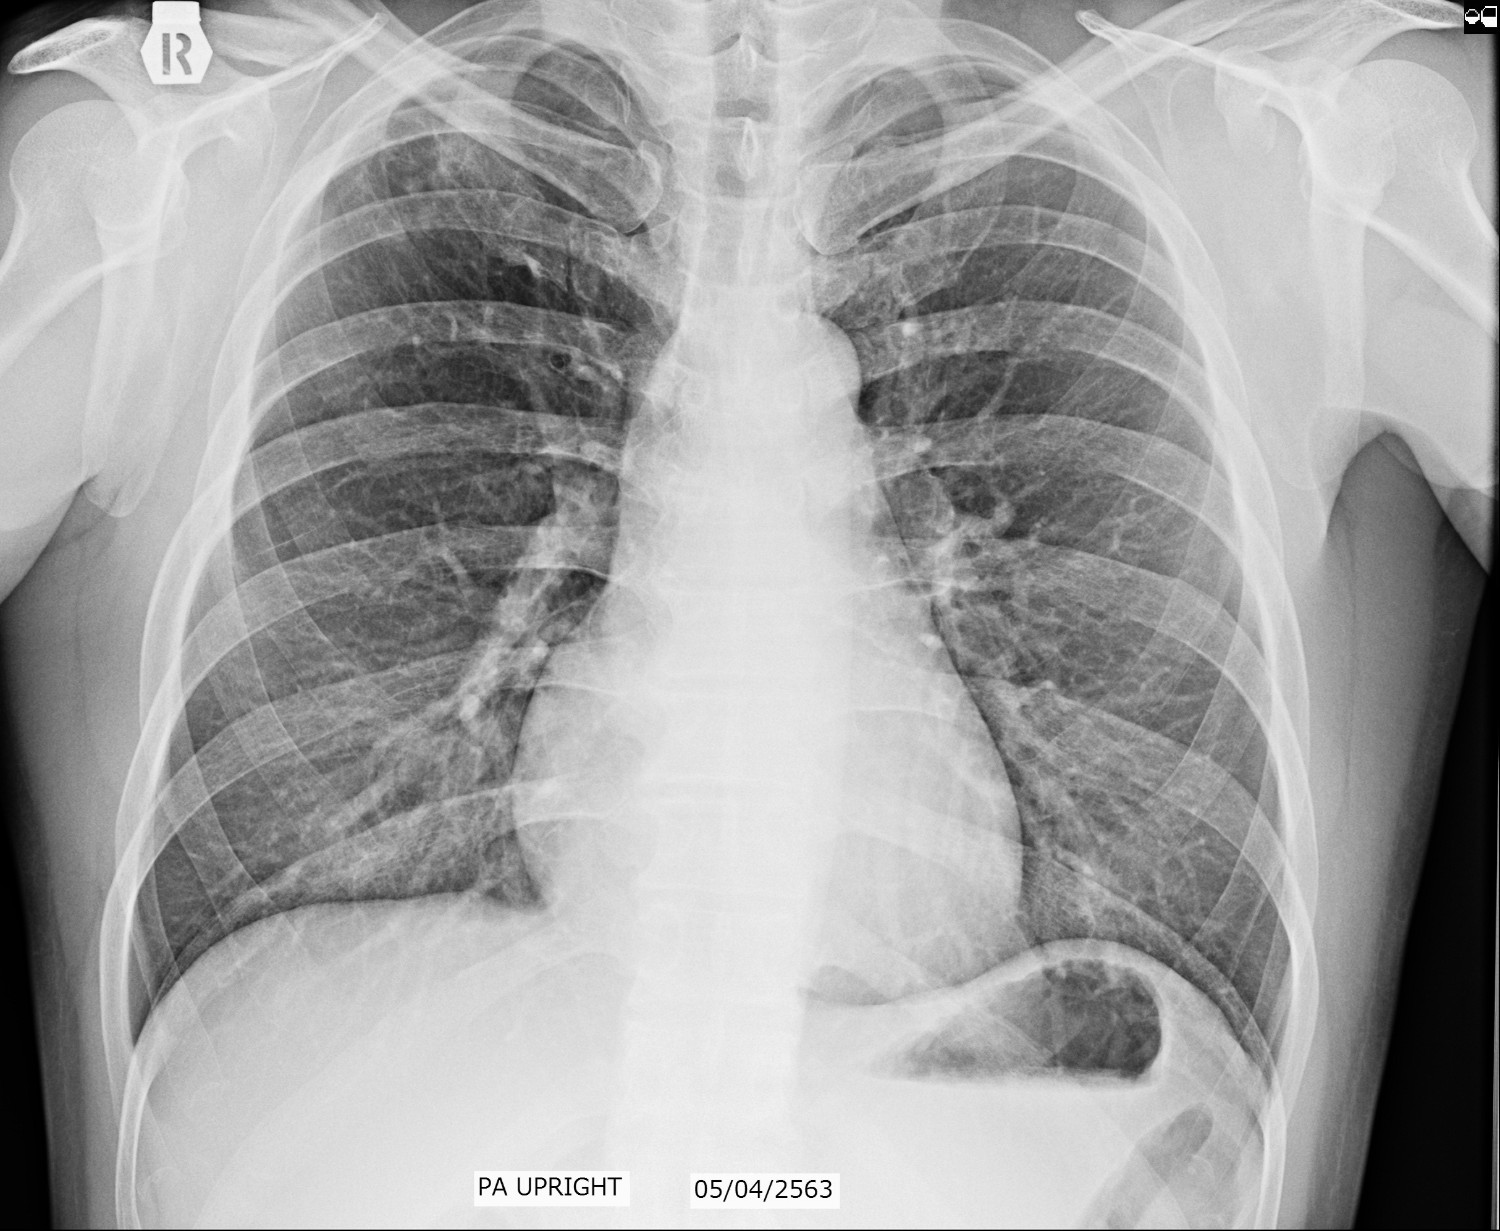

ผมกำลังรักษาตัว TB อยู่ครับ ตั้งแต่ พย 62 ที่ผ่านมาจน ถึงบัจุบัน 24 พค 63 ทานยามมาแล้ว 6 เดือน คุณหมอให้ทานยาต่ออีก 2 เดือนเพื่อความชัวร์

ตรวจเสมหะไม่เคยเจอเชื้อ คุณหมอให้เข้ารับการรักษาเพราะผลฟิลม์ บ่งชี้ชัดเจนครับ ส่วนอาการไอไม่เคยมีเลย

ฟิลม์เรียงวันที่ 26 มค 63,  5 เมษา 63. และ 24 พค 63 ครับผม. กราบขอบพระคุณในความอนุเคราะห์ล่วงหน้าครับผม